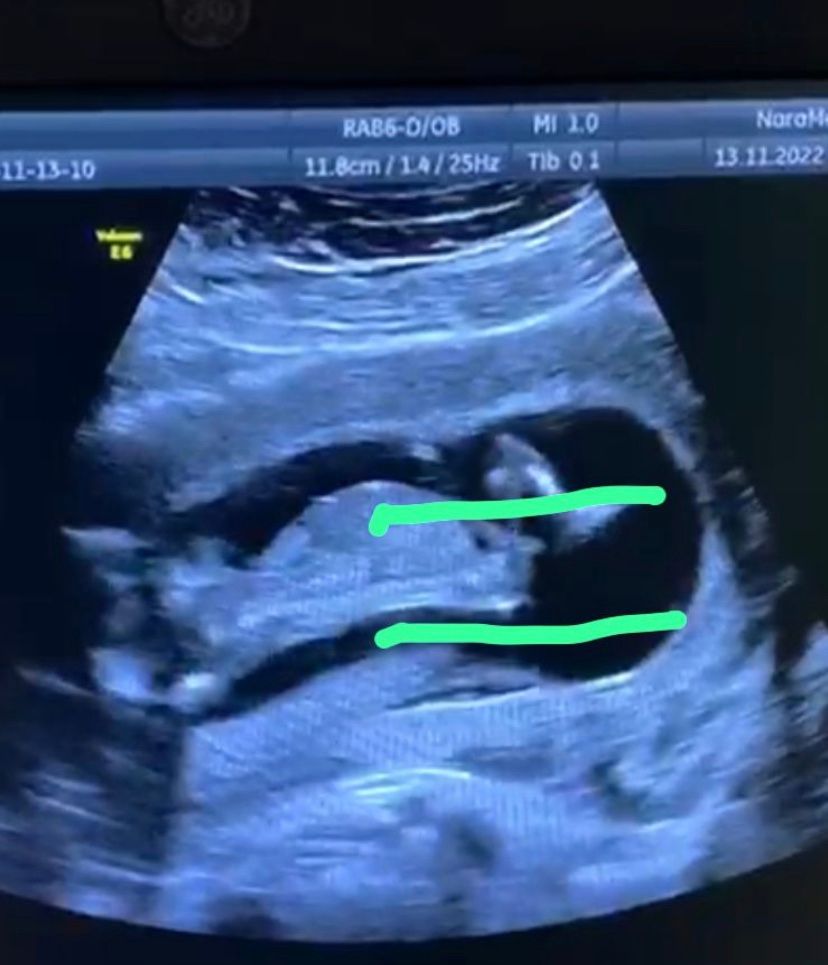

Девочки выслушаю все ваши догадки, как думаете кто будет мальчик или девочка 😗

Елена , хорошо видно половой бугорок (вроде это он)) практически горизонтально, а это девчуля. А узист, что говорит?

Nina, что вроде бы мальчик

Елена , хм, может ракурс такой и не видно угол наклона хорошо... Нет фото в профиль? 😊

Я за девочку! Не верные свои догадки сначала писала.. сравнила со своей фоткой в дневнике - пусть будет девочка!))) Изображение